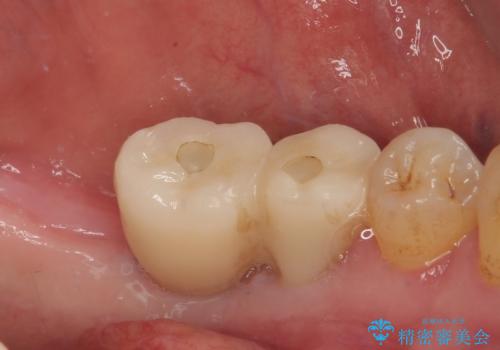

連結の手前の歯は歯根が破折して、クラウンが歯から外れており、奥の歯は動揺により歯根周辺の骨が吸収している状態でした。

骨吸収が甚大な後方は3ヶ月ほど待機して、手前は抜歯即時埋入により、短期間インプラント補綴治療を行うこととしました。

なお、後方の歯は痛みが酷かったため、初診時に抜歯をすることとなりました。